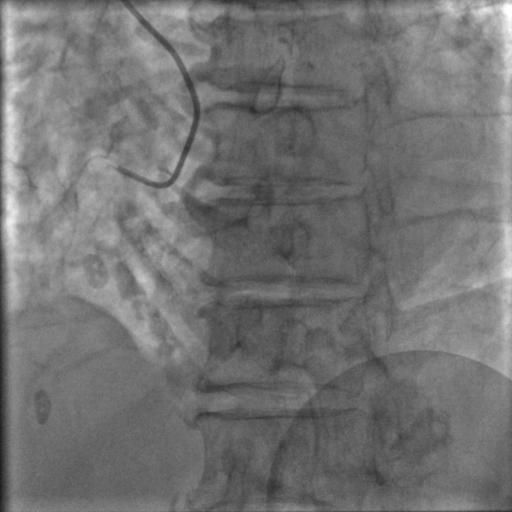

常规消毒、铺巾,再穿刺、放鞘管、送入造影导管、造影,一切顺利,造影结果如下:

图2

图3

图4

比我们想象中的要好,前降支中段闭塞,第一、第二对角支都还在,回旋支、右冠都还好,可以稍微松一口气。